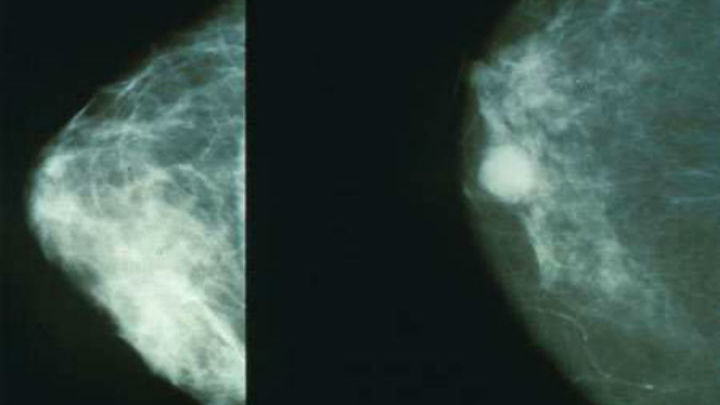

Гистологическая характеристика

У кошек 85-95% новообразований молочных желез являются злокачественными (фото 1). Доброкачественные патологии и опухоли встречаются в 5-15% и к ним относят такие гиперпластические и диспластические процессы, как фиброэпителиальная гиперплазия, лобулярная гиперплазия, протоковая эктазия молочных желез (Hayfen DW. et al. 1971; Misdrop W.